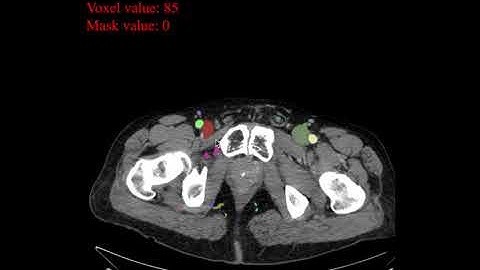

Segmenting abdominal organs with MedSeg